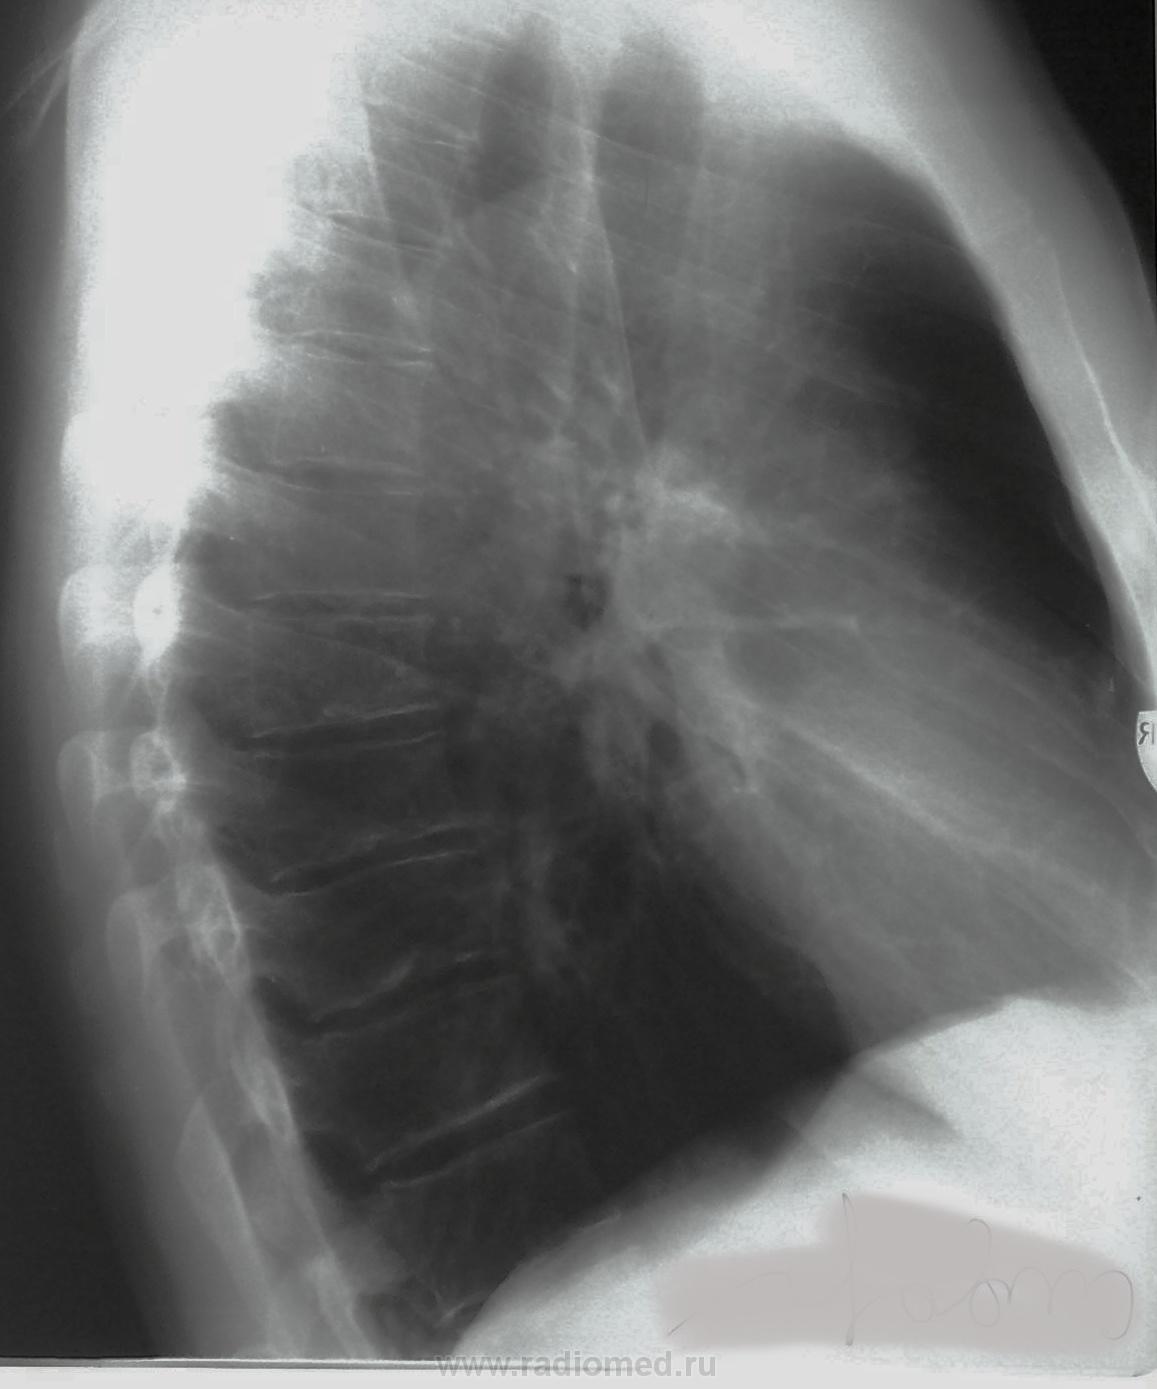

Направлен в ПТД, " очаговая тень справа". Что-то фтизиатр после 2нед. обследования стал "выталкивать" к онкологу.

за 3 ребром? качество страдает конечно.По боковому Шоерман-Мау. "Трудно искать черную кошку..."

Можно предположить артерио-венозную аневризму (мальформацию).Непложо было бы ФЛО- архив посмотреть, в плане давности изменений. Вы сами на скопии пациента не смотрели?

yes Онкологи без КТ не берут, сегодня выложу КТ. То же думаю за мальформацию.

Плюсую за мальформацию

Эта штука онкологу не нужна. При пробе Вальсальвы и Мюллера должны изменится размеры аневризмы.